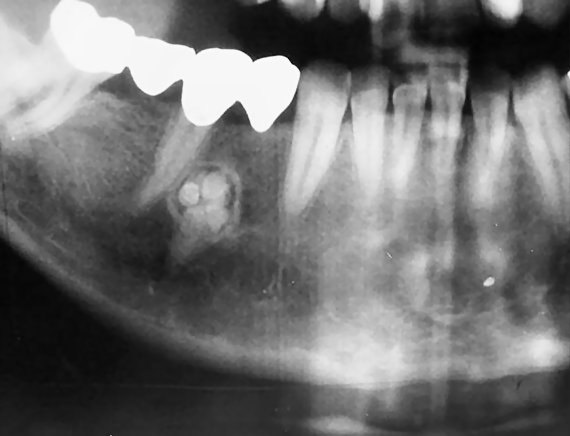

Odontoma (mixed) .

- Two types: complex and compound odontoma.

- Complex odontoma is composed of haphazardly arranged dental hard tissues.

- Compound odontoma is composed of many small “denticles”

- Failure of eruption of a permanent tooth may be the first presenting sign. It is commonly found peri-coronal to the impacted tooth.

- Well defined borders. The internal pattern of the lesion is more radiopaque compared to the normal bone.